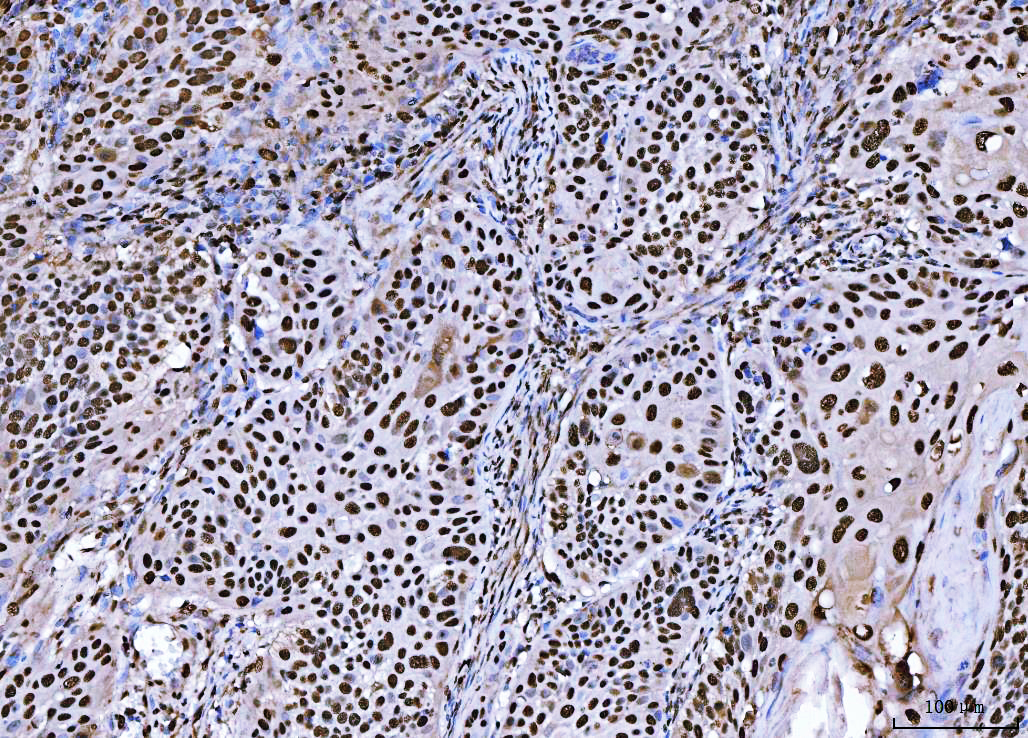

IHC analysis of BRCA1 using anti-BRCA1 antibody (PB9015).

BRCA1 was detected in a paraffin-embedded section of human laryngeal squamous cell carcinoma tissue. The tissue section was incubated with rabbit anti-BRCA1 Antibody (PB9015) at a dilution of 1:200 and developed using HRP Conjugated Rabbit IgG Super Vision Assay Kit (Catalog # SV0002) with DAB (Catalog # AR1027) as the chromogen.